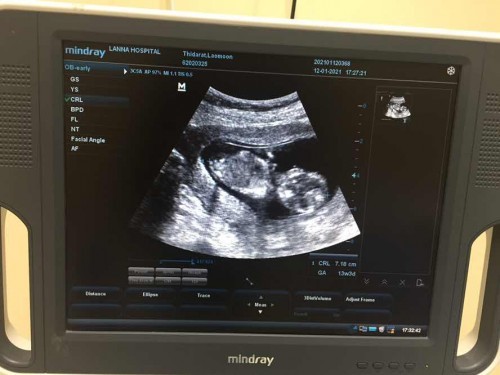

ความสูงของลูกในครรภ์ สูงกว่าเกณฑ์ที่คำนวณจะเป็นอะไรไหมคะ เช่นตามเณฑ์สูง7.4ซม. แต่อัลตร้าซาวน์ออกมาได้7.18ซม. อายุครรภ์13W 3D

ภาพอะลตร้าซาวน์13W3D

สรุปสูงกว่าเกณฑ์หรือต่ำกว่าเกณฑ์ งง เกณฑ์ 7.4 วัดได้ 7.18